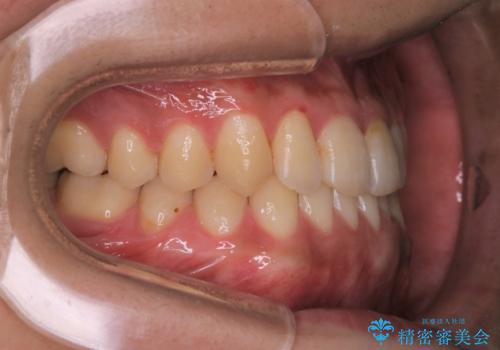

- 矯正治療が終わったので歯のクリーニングを希望され来院しました。

PMTC60分コースを行いました。

全体の歯の面に着色がついていました。PMTCを定期的に行うことにより、毎日の歯磨きやお食事によって傷ついた歯をツヤツヤでなめらかな歯にしてくれます。ですので着色が付着しにくい歯にすることができます。